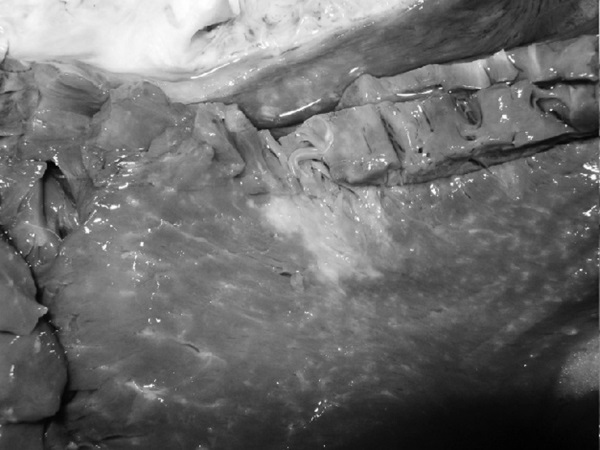

На секции был установлен следующий диагноз.

Основной:

1. Последствия инфаркта головного мозга. Внутренняя гидроцефалия. Атеросклероз артерий виллизиева круга.

2. ИБС. Постинфарктный кардиосклероз. Атеросклероз коронарных артерий.

Фоновый:

1. Артериальная гипертензия.

2. Гипертрофия левого желудочка сердца.

Осложнения:

1. Длительная иммобилизация.

2. Хроническая сердечная недостаточность.

3. Невроангиосклероз.

4. Пролежни.

5. Интоксикация.

6. Отек головного мозга.

Сопутствующий:

Доброкачественная гиперплазия предстательной железы

Последствия ОНМК: постинфарктные кисты головного мозга

Постинфарктный кардиосклероз

Атеросклероз сосудов головного мозга. Отек головного мозга

Атеросклероз коронарных артерий

Гипертрофия левого желудочка

Мускатная печень

Полнокровные легкие

Рис. 1. Результаты аутопсии больного 68 лет